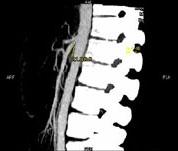

问题 女 ,24 岁,发作性肉眼血尿1 年,实验室检查:尿蛋白 (- +)、红细胞1 2/HP,尿蛋白直立试验 (+),CT扫描如图,下列说法正确的是 ( )

选项 A、左侧肠系膜上动脉与腹主动脉夹角增大 B、考虑为左肾静脉胡桃夹综合征 C、左肾静脉走行至肠系膜上动脉与腹主动脉间变细,近左肾处扩张 D、左侧肠系膜上动脉与腹主动脉夹角变小 E、双肾大小形态正常

答案 BCDE